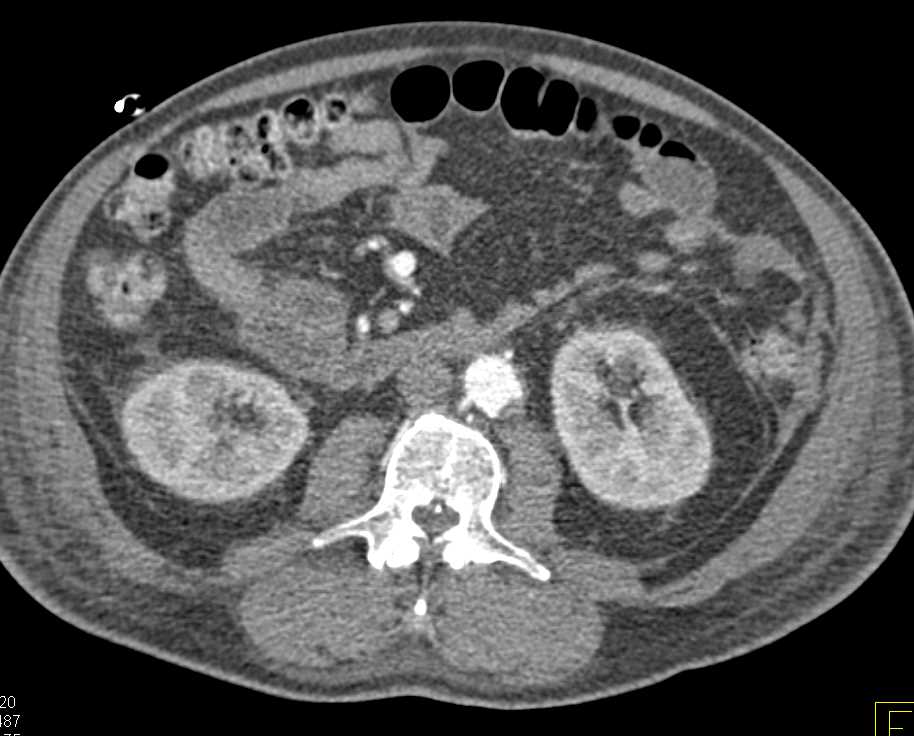

Gastric GIST Tumor with Carcinomatosis